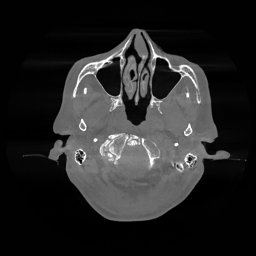

The results for simulated noisy data are shown in Fig. 2. The first and third rows display two representative slices from the test set, and the second and fourth rows present the corresponding error maps. The traditional WCE method suppresses cupping artifacts and recovers some missing anatomical structures but still shows noticeable deviations from the ground truth. Predictions from the four diffusion-based models demonstrate a markedly improved ability to restore anatomical structures. Among them, cDDPM fails to fully reconstruct the patient bed and retains residual noise in its outputs. This noise is attributable to an incomplete reverse denoising process rather than residual Poisson noise, as evidenced in our noise-free experiments (Fig. 5 in the Appendix). PatchDiffusion, diffusionGAN, and I2SB achieve similar visual quality, with I2SB producing the cleanest and most consistent reconstructions.

The experimental results on clinical head data are shown in Fig. 4. The reference images were reconstructed using the fast iterative shrinkage-thresholding algorithm (FISTA) with total variation regularization from non-truncated projection data. In the WCE reconstructions (Fig. 4(b)), severe truncation prevents accurate recovery of anatomical structures outside the FOV. Despite being trained solely on simulated data with a domain gap, all deep learning models can restore a substantial portion of the missing anatomy. Among them, the diffusion-based methods recover soft-tissue boundaries more faithfully than the conventional deep learning approach FBPConvNet, highlighting their stronger image generation capability. However, cDDPM reconstructions exhibit more noticeable noise than those from other methods, consistent with the simulated data results. The patchDiffusion model introduces artifacts within the FOV, likely due to its patch-wise processing strategy. While I2SB shares the same limitations as other diffusion models in perfectly restoring soft-tissue detail, it produces fewer residual noise patterns and fewer artifacts within the FOV boundaries. Overall, Fig. 4 demonstrates the strong efficacy of I2SB in reconstructing real CBCT data.